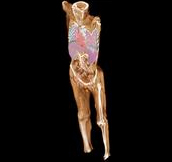

Whole body scanning (1,700mm) can be done in 10 sec.

0.35sec, BP 0.83, 5mm slice width, 500mA (175mAs), only 6.5 sec from lung ? pelvis with 0.35sec/rot